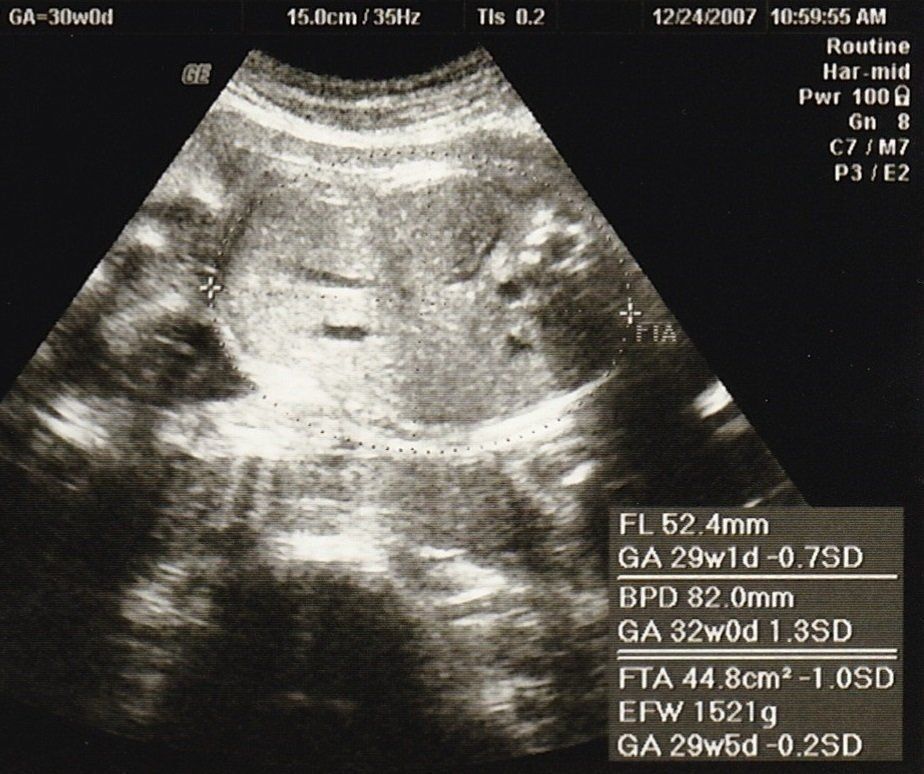

妊娠30週目のエコー写真

赤ちゃんの大きさは標準の真ん中あたり。胎盤の位置や羊水の量も正常、母子ともに問題はありませんでした。